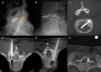

Procedimientos diagnósticosEn la figura 2 se exponen ejemplos de discografía y biopsia.

A) Discografía normal. La distribución de contraste se ubica exclusivamente en el núcleo pulposo (flecha). B) Discografía. Disco degenerado con contraste en núcleo pulposo y anillo fibroso. C) Biopsia coaxial en una discitis. D) Biopsia coaxial en un tumor de células gigantes del arco vertebral. E) Biopsia transpedicular en una metástasis de mama. F) Biopsia coaxial en una leucemia del saco tecal.

La discografía se utiliza para el diagnóstico del dolor de origen discógeno, cuya prevalencia se estima entre el 26-39% de los pacientes con dolor lumbar crónico sin síntomas radiculares10.

Generalmente se utiliza como técnica previa a la artrodesis quirúrgica, para determinar aquellos discos intervertebrales que deben incluirse en la fijación. La aproximación al disco suele hacerse guiada mediante fluoroscopia, por vía posterolateral derecha a nivel lumbar y anterolateral derecha a nivel cervical, con agujas 22-23G. La aguja se debe colocar en el centro del disco, donde se inyectan entre 1-3cc de contraste a nivel lumbar y 0,5-1,5 a nivel cervical. El paciente debe relatar si la inyección de contraste le provoca dolor, su intensidad y si este dolor es similar al que él padece habitualmente10.

Morfológicamente el disco se evalúa en la fluoroscopia y con una TC que permite delimitar el grado de degeneración discal, la presencia de fisuras y su grado de extensión en el anillo fibroso. Estas alteraciones morfológicas se consideran menos relevantes que la provocación del dolor en la toma de decisiones. Los criterios aceptados por la International Association for the Study of Pain para diagnosticar el dolor discógeno es la reproducción de los síntomas del paciente con la estimulación del disco, mientras que la inyección en los 2 discos adyacentes no provoca dolor3.

BiopsiaEn los pacientes con tumor conocido la biopsia se puede utilizar para confirmar la afectación metastásica o para determinar en la muestra la existencia de marcadores tumorales que orienten hacia un tratamiento específico. En ausencia de tumor primario conocido la biopsia es importante para el diagnóstico inicial y la planificación del abordaje terapéutico.

Las técnicas percutáneas guiadas por imagen ofrecen grandes ventajas sobre las técnicas quirúrgicas: posibilidad de obtener muestras de regiones más profundas, en las áreas no necróticas, el uso de anestesia local, menor demora en el inicio de la radioterapia, etc.11.

Generalmente se debe usar una técnica coaxial: a la lesión se aproxima una cánula gruesa y corta que permita extraer varias muestras con una trefina más delgada y larga. Bajo control de TC la vía posterolateral es la más utilizada, aunque también es factible la vía transpedicular.

La rentabilidad diagnóstica se incrementa obteniendo un mínimo de 3 muestras en lesiones óseas y 4 en las lesiones de partes blandas12. La exactitud diagnóstica se define como la capacidad de hacer un diagnóstico correcto en la muestra y se determina como el porcentaje entre verdaderos positivos y negativos con respecto al total de la muestra. En las biopsias percutáneas de columna es superior al 80%11, mayor en lesiones osteolíticas que en osteoblásticas, y también en metástasis que en tumores primitivos. En la infección la exactitud suele ser menor porque muchos casos se puncionan posteriormente al inicio del tratamiento antibiótico13.